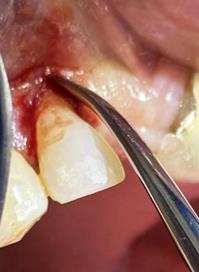

Figura 8. Irrigación del alveolo con solución fisiológica y sutura simple en la mitad del alveolo.

Elaboración: Los autores.

Finalmente se prescribió al paciente ibuprofeno de 600 mg por cuatro días, se le manifestó instrucciones postoperatorias y control para remoción de puntos en una semana.